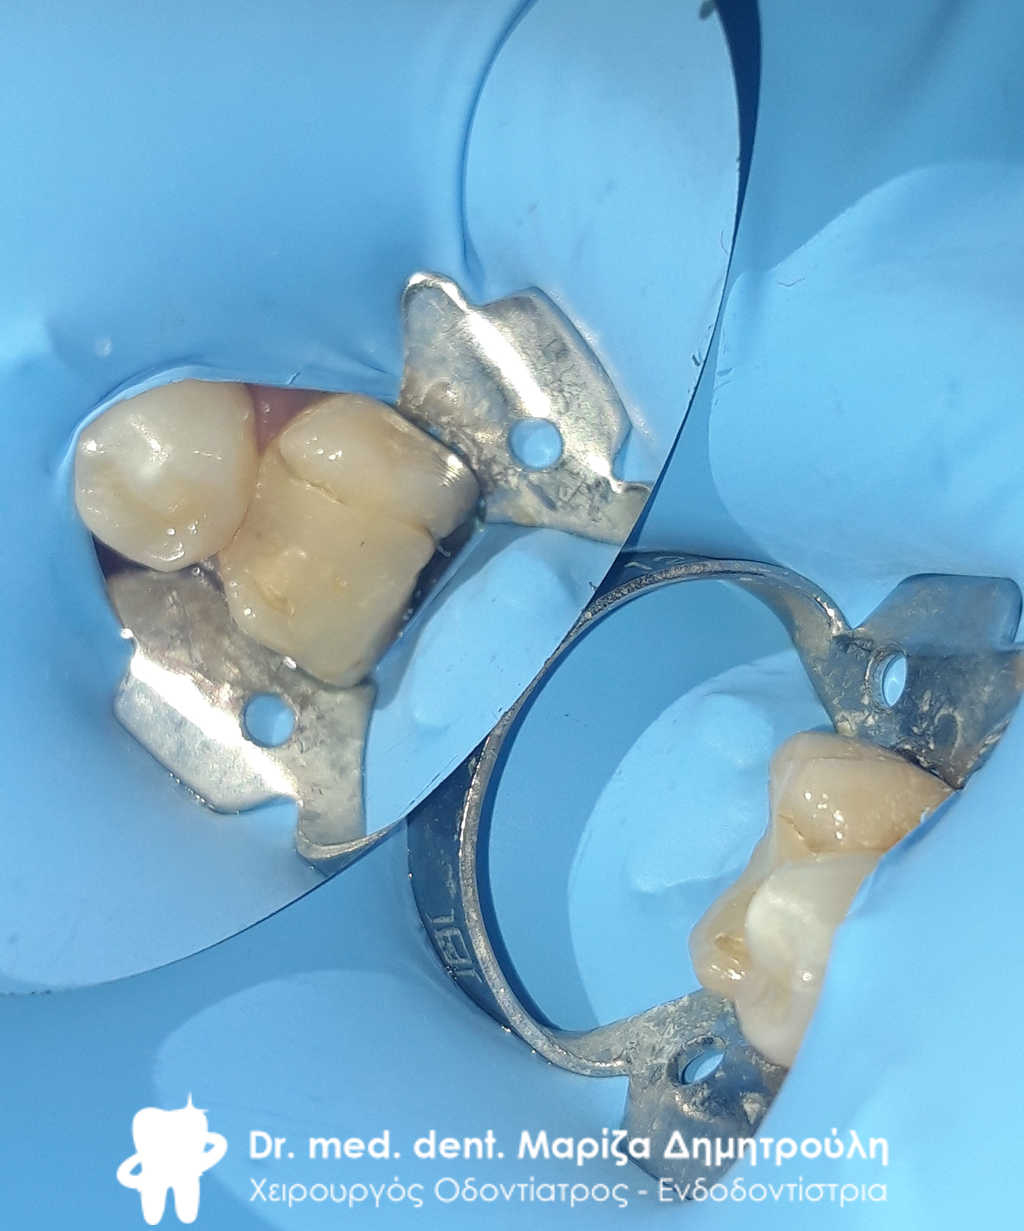

ΠΡΙΝ – Παλιά μαύρα σφραγίσματα

Το δόντι με τον απομονωτήρα. Διακρίνονται 4 ριζικοί σωλήνες